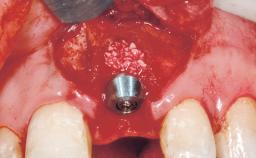

A 30-year-old female patient was referred to the office for the treatment of tooth 11. Her chief concern at the initial visit was to inquire, “Why is my tooth pink?” Upon clinical examination, it was determined that tooth 11 had a previous history of trauma and that the clinical crown had become noticeably pink in color as a result of internal resorption. This diagnosis was confirmed radiographically, indicating a large radiolucency involving the central and distal portions of the clinical crown. It was determined that restoration of this tooth was not possible, and that extraction was indicated. The presence of a mid-line diastema, which the patient wanted to reproduce, directed the treatment plan for tooth replacement utilizing a dental implant.

| Placement Protocol | Immediate implant placement |

| Socket Morphology | Single-root socket |

| Socket Integrity | Sufficient, with intact bone walls |

| Bone Volume | Sufficient, with intact walls |